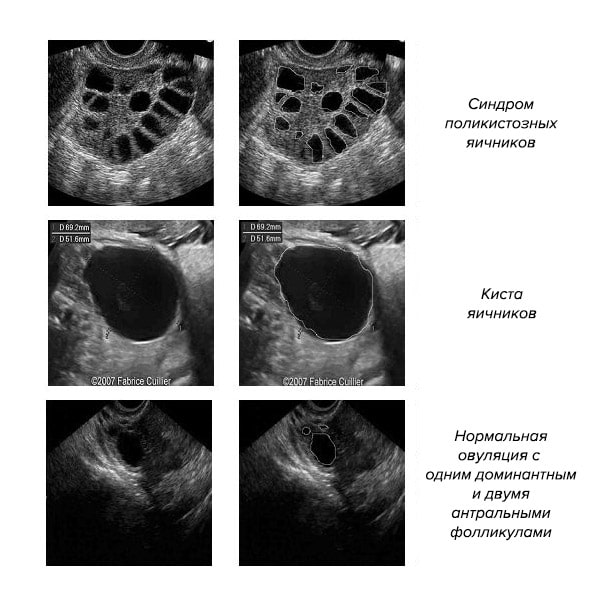

В процессе трансвагинального сканирования УЗИ доктор получает ясную картину размеров женских внутренних половых органов и их структуры. При наличии заболевания наблюдается уменьшение матки по толщине, ширине и длине. Структура матки остается однородной. Яичники значительно уменьшены в размере, имеют гомогенную структуру, фолликулы в них не визуализируются.